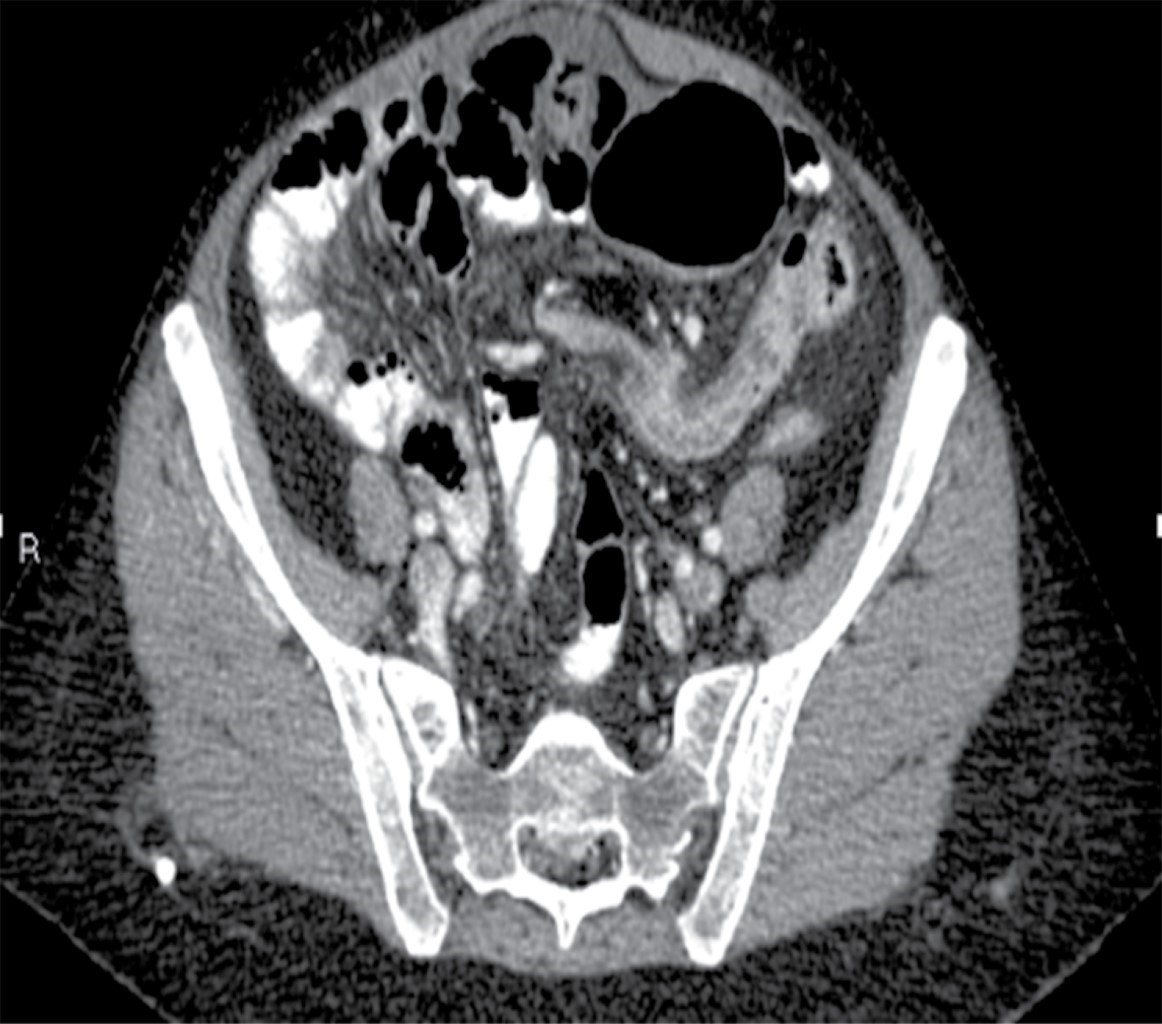

Se solicitaron estudios de laboratorio, los cuales reportaron 12,000 leucocitos por milímetro cúbico, siete bandas y niveles de lactato sérico de 2.8 mmol/l. Posteriormente se realizó una tomografía de abdomen con doble contraste, encontrando importante dilatación cecal, dilatación de colon ascendente y de la porción proximal de colon transverso, junto con una zona de transición hacia tercio distal, localizado en fosa iliaca izquierda. De igual manera, se encuentra hernia de pared abdominal supraumbilical en línea media con escaso tejido graso y epiplón (Figuras 1, 2, 3 y 4).

Figura 2